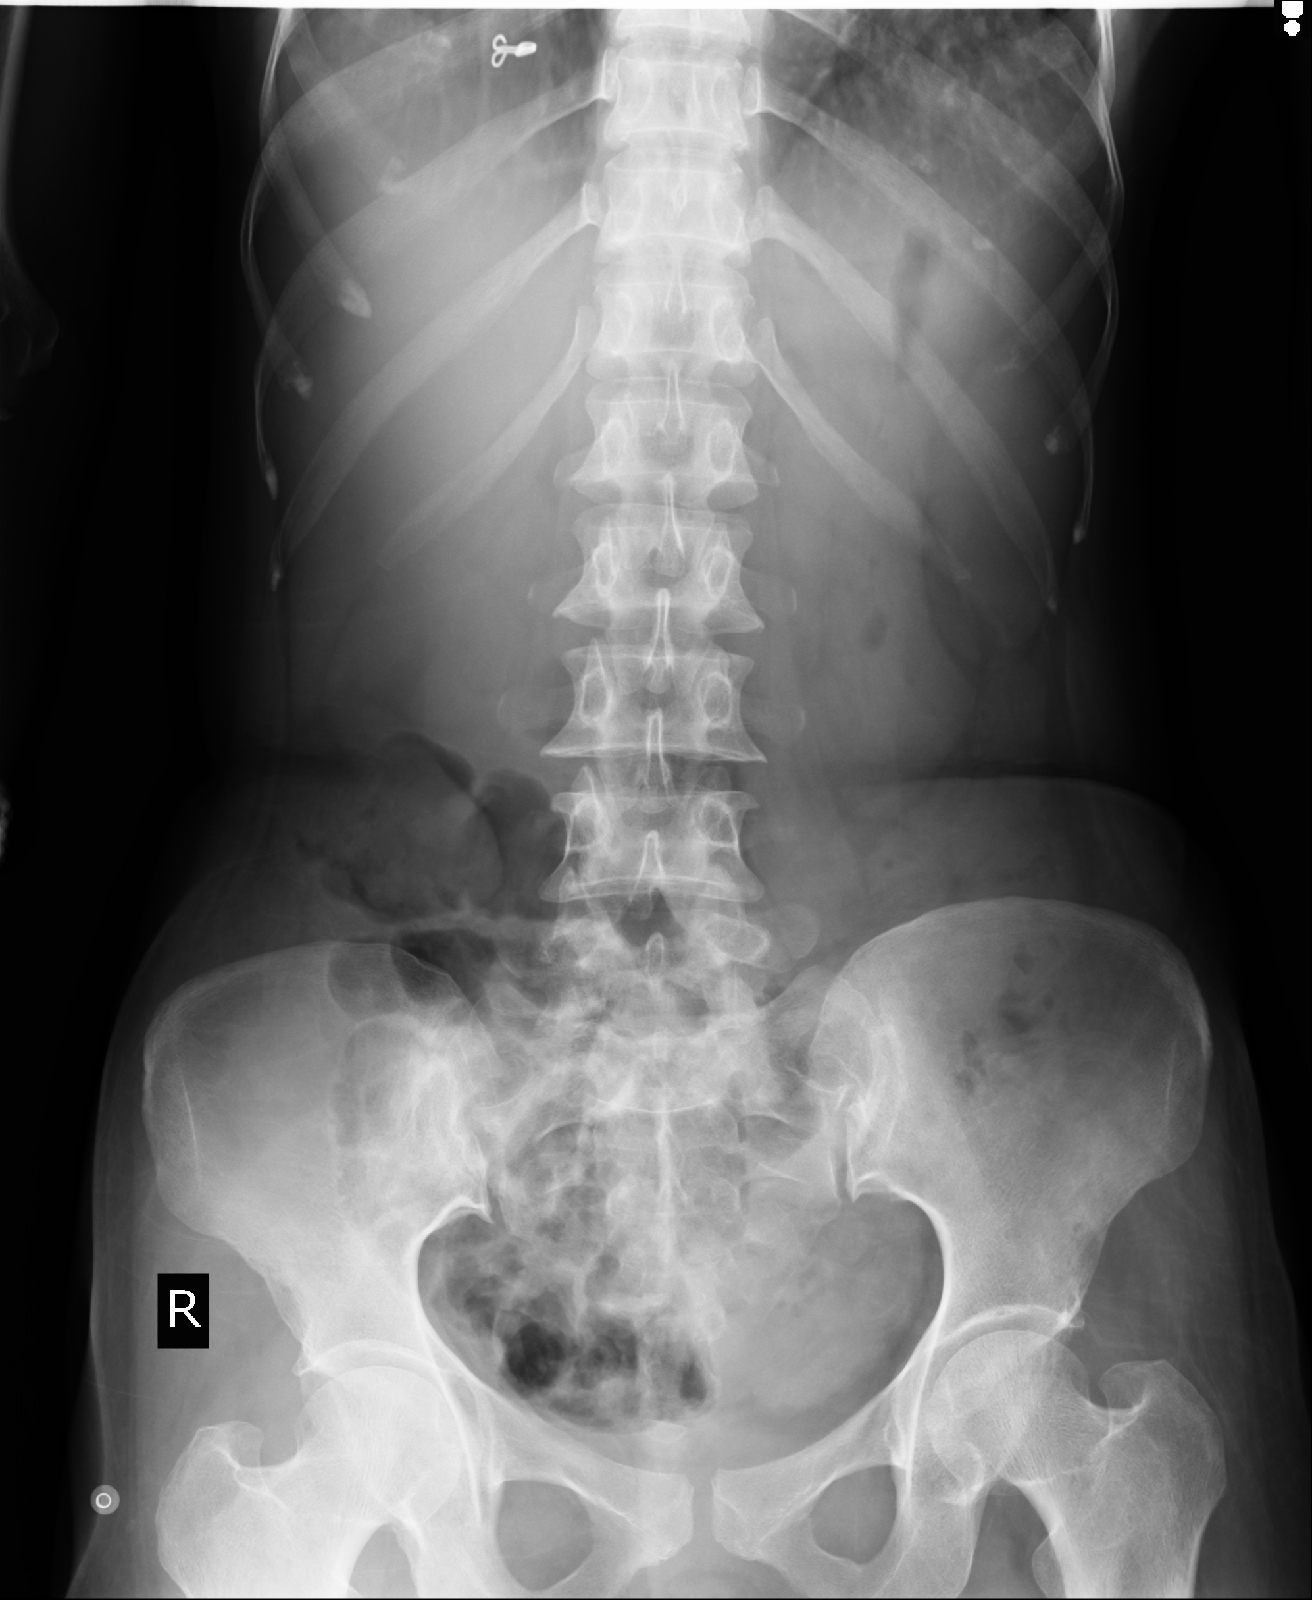

49 year female with fever

Fever since 15 days.

Abdominal discomfort since 15 days.

Generalized weakness since 15 days.

Decreased appetite since 15 days.

A 49 year female presented to the OPD with complaints of high grade Intermittent fever associated with chills, malaise and decreased appetite. Fever was relieved on taking medication. History of abdominal discomfort as tightness since 15 days not associated with vomiting. History of nausea associated with decreased appetite. No history of headache, retro orbital pain, cold, cough, chest pain, SOB, PND, Orthopnea, burning micturition.

P/A: Soft, Upper abdominal tenderness, BS+;